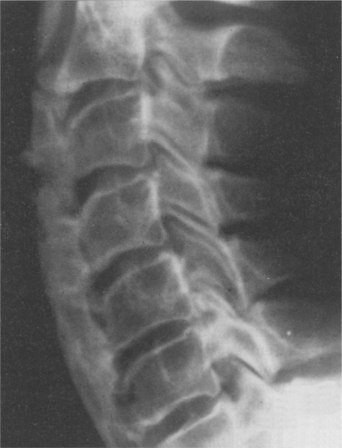

SPINE.: Diffuse idiopathic skeletal hyperostosis (DISH; also known as ankylosing hyperostosis or Forestier disease) is a condition of the spine seen most often in people with type 2 DM, although it can occur in a person who does not have diabetes. In DISH, osteophytes develop into bony spurs, typically right-sided syndesmophytes that may join to form bridges (Fig. 11-12). The thoracic spine most commonly is involved. In contrast to ankylosing spondylitis, the sacroiliac joints are spared, and vertebral body osteoporosis is absent. Calcaneal and olecranon spurs may develop, and new bone may form around hips, knees, and wrists.

Figure 11-12 Diffuse idiopathic skeletal hyperostosis (DISH), or ankylosing hyperostosis, associated with type 2 diabetes mellitus (DM). DISH can occur with other conditions such as ankylosing spondylitis. Although the dense anterior bony bridging of the cervical vertebrae is pictured on this lateral roentgenogram, the thoracic spine most commonly is involved in diabetes. This type of DISH can be distinguished from ankylosing spondylitis by the preservation of sacroiliac joints, a site of typical involvement in ankylosing spondylitis. (From Kaye T: Watching for and managing musculoskeletal problems in diabetes, J Musculoskel Med 11:25-37, 1994.)

People with DISH may be asymptomatic or they may experience back pain and stiffness without limitations in range of motion. Dysphagia may develop if extensive cervical spine involvement occurs. The pathogenesis of DISH is unknown, and apparently no correlation exists between the degree of diabetic control and the extent of hyperostosis.